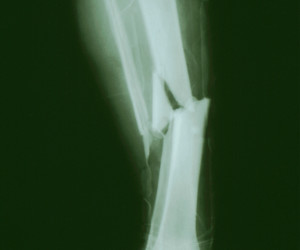

Broken leg bone